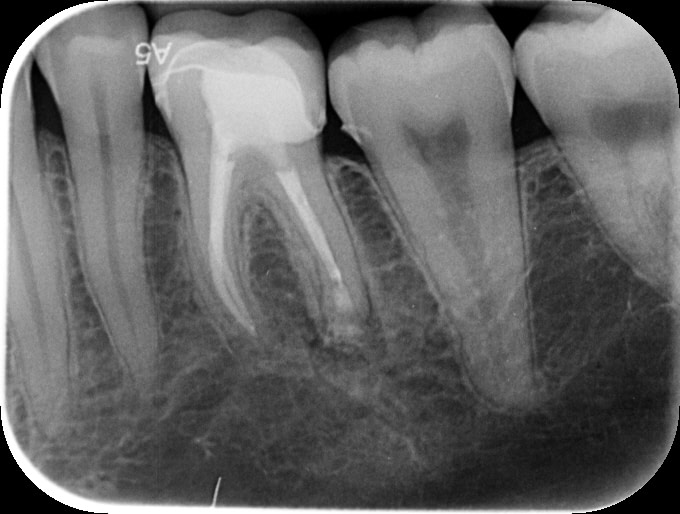

Post-operative Outcome

Post op PA showing completed apicectomy with retrograde MTA putty root filling and bone graft.